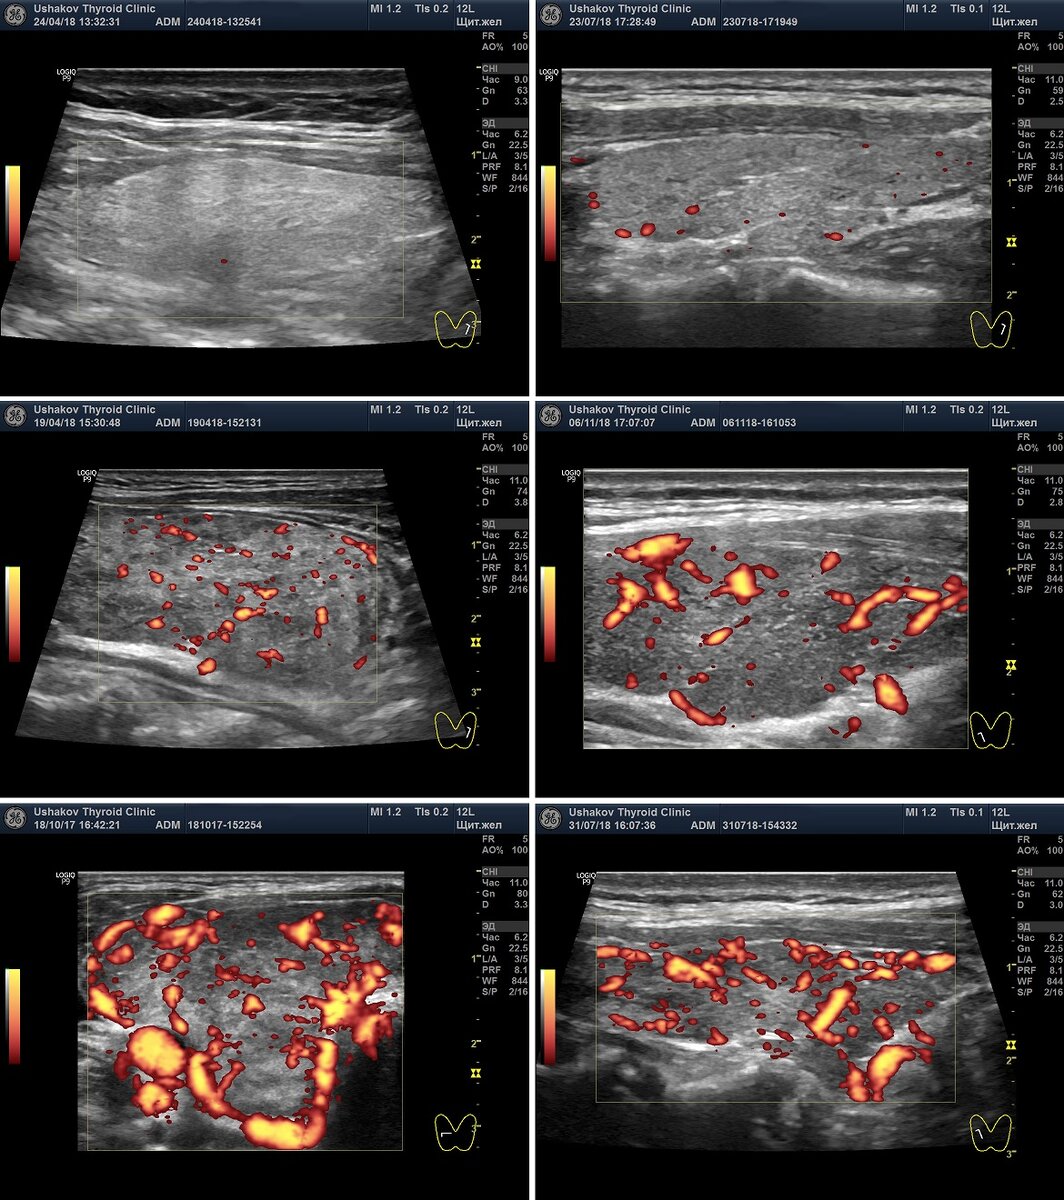

Посмотрите как может отличаться интенсивность кровотока в щитовидной железе при ЭДК

Во время УЗИ щитовидной железы врач обязан провести допплерографическое исследование каждой доли и перешейка, а также определить скорость кровотока в сосудах железы. Это исследование врачи обозначают аббревиатурой ЦДК или ЭДК (ЭД). ЦДК - цветовое допплеровское картирование, ЭДК - энергетическое допплеровское картирование (иногда применяют краткое обозначение - ЭД). ЭДК более точно, без искажений, позволяет определять кровоток. Следует знать, что допплеровское исследование щитовидной железы является обязательной, важной частью при УЗИ. Оно должно входить в стоимость УЗИ, а его результаты должны быть отражены в Протоколе УЗИ, к которому приложены снимки в режиме ЦДК или ЭДК, где видны сосуды. Врачи часто применяют термин ВАСКУЛЯРИЗАЦИЯ для обозначения состояния сосудистой сети железы в Протоколе УЗИ. Слово "васкуляризация" дословно означает - СОСУДИСТОСТЬ. Это прямое заимствование из англоязычной литературы. Поэтому воспринимается врачами привычно, но означает именно сосудистость, а не

Во время УЗИ щитовидной железы врач обязан провести допплерографическое исследование каждой доли и перешейка, а также определить скорость кровотока в сосудах железы. Это исследование врачи обозначают аббревиатурой ЦДК или ЭДК (ЭД).

ЦДК - цветовое допплеровское картирование, ЭДК - энергетическое допплеровское картирование (иногда применяют краткое обозначение - ЭД).

ЭДК более точно, без искажений, позволяет определять кровоток.

Следует знать, что допплеровское исследование щитовидной железы является обязательной, важной частью при УЗИ. Оно должно входить в стоимость УЗИ, а его результаты должны быть отражены в Протоколе УЗИ, к которому приложены снимки в режиме ЦДК или ЭДК, где видны сосуды.